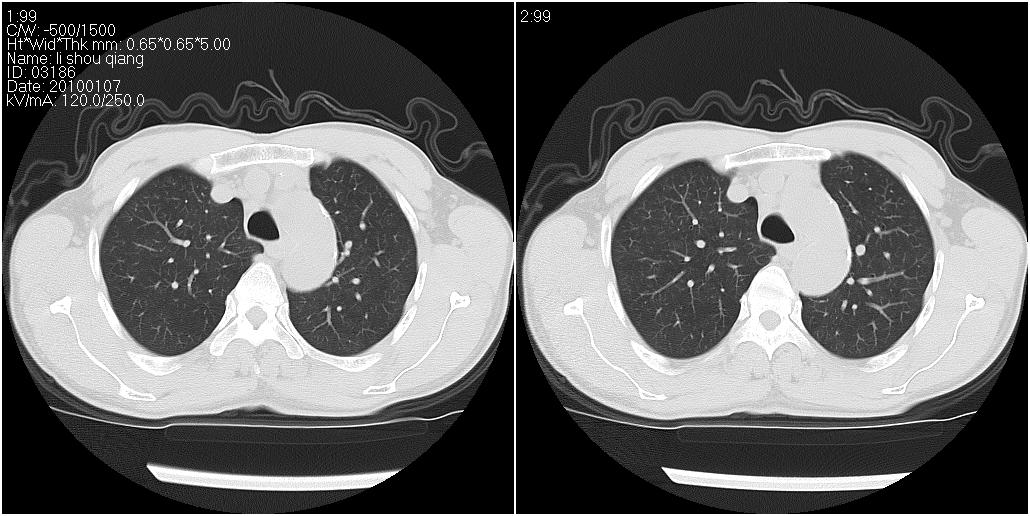

标题: CT24038:男性,58岁。主因咳嗽带血性CT检查。 [打印本页]

标题: CT24038:男性,58岁。主因咳嗽带血性CT检查。

右肺中叶外侧段见一不规则的软组织肿块,边缘可见毛刺,并见厚壁空洞,与胸膜分界欠清。另左下肺见多个小囊状扩张区

右肺中叶外侧段可见团块影,外形不规则,内见空泡征。左下肺见蜂窝状低密度透亮影,部分层面主动脉旁瘤样突出。考虑右肺中叶外围型肺癌可能性大,左下肺支气管扩张,主动脉弓瘤样突出。

1、右肺中叶病灶内不规则气体影、低密度影,且与胸膜接触面宽,病灶边缘模糊。考虑右肺中叶感染并有脓肿形成。建议抗炎治疗后复查。2、左下叶支气管扩张症。

1、右肺中叶病灶周围有炎性反应,所以考虑感染病灶,建议增强扫描进一步鉴别 2、左肺支扩